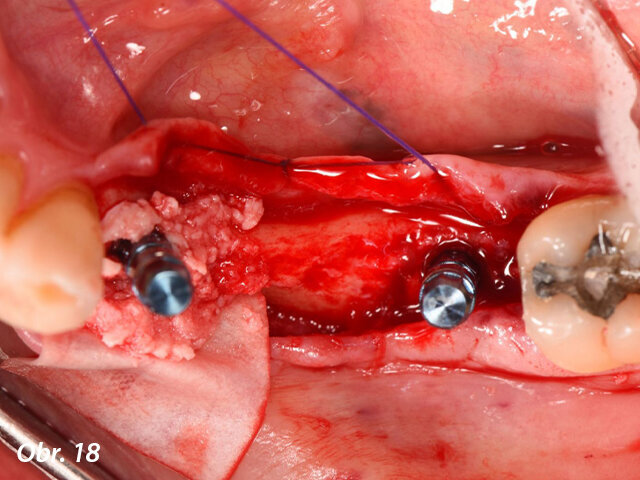

Kromě toho byla ve vestibulární oblasti implantátu v oblasti zubu 34 současně provedena augmentace za použití membrány Straumann Jason a kostního štěpu. Důvodem této horizontální augmentace byla tenká (méně než 1,5 mm) zbytková kost ve vestibulární oblasti (obr. 15). Kolagenní membrána byla stabilizována pomocí zirkonového vhojovacího abutmentu (RC ø 4,5 mm, výška 4 mm), zatímco pro implantát v oblasti zubu 36 byl našroubován titanový vhojovací abutment (RC ø 4,5 mm, výška 4 mm). Laloky byly uzavřeny umístěním jednoduchých stehů Vicryl 5/0 (obr. 16–20).